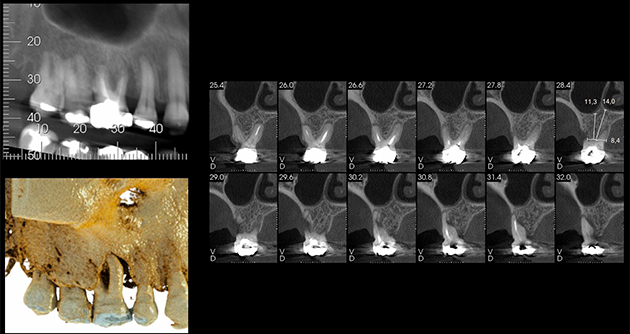

Na avaliação clínica, verificou-se o extravasamento de pus via sulco gengival no dente 16. A paciente relatava dor à palpação local e durante a percussão. Além disso, o dente 16 apresentava mobilidade grau 1, fratura de cúspides, uma extensa restauração de amálgama, lesões cariosas próximas à restauração e acúmulo de biofilme. O exame tomográfico revelou uma lesão envolvendo a raiz mesiovestibular do dente 16, com provável comunicação endoperiodontal.

3 | Exame tomográfico da região do dente 16.